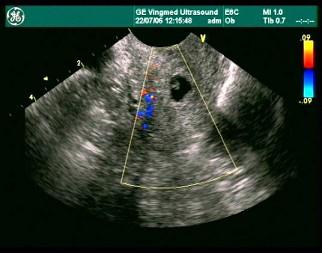

女性,32岁,因停经42天行超声检查,经阴道超声检查提示,初步判断为?(?)A.宫颈妊娠B.宫颈囊肿C.黄体囊肿D.葡萄胎E.以上都不对

问题 女性,32岁,因停经42天行超声检查,经阴道超声检查提示,初步判断为?(?)

选项 A.宫颈妊娠 B.宫颈囊肿 C.黄体囊肿 D.葡萄胎 E.以上都不对

答案 A